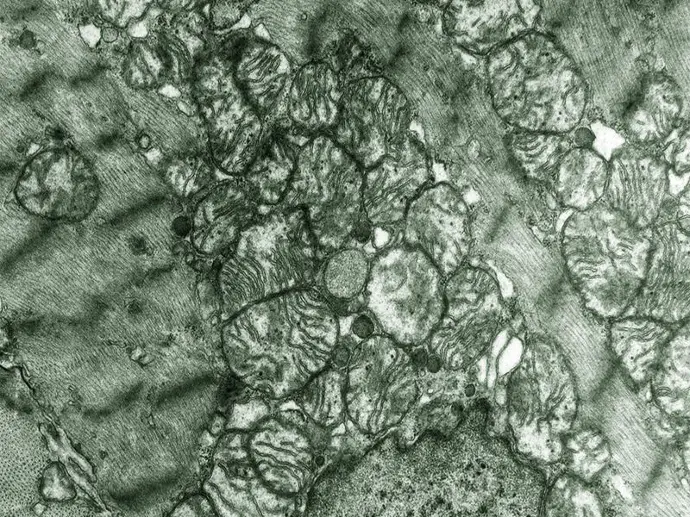

In den Mitochondrien laufen zahlreiche zentrale Stoffwechselprozesse ab. Besonders bekannt ist die mitochondriale Atmungskette, die etwa 90 % der Energie für den Körper in Form von ATP bereitstellt. Da ATP kaum gespeichert werden kann, wird es ständig neu gebildet. Der tägliche ATP-Verbrauch entspricht dabei ungefähr dem eigenen Körpergewicht – bei einem Körpergewicht von 70 kg produzieren die Zellen also täglich etwa 70 kg ATP!

Damit diese Prozesse reibungslos ablaufen können, müssen die Proteine, Enzyme, mitochondriale DNA und auch die Membranen ‒ v. a. auch die innere Mitochondrienmembran, in der die Energiegewinnung stattfindet ‒ intakt sein.